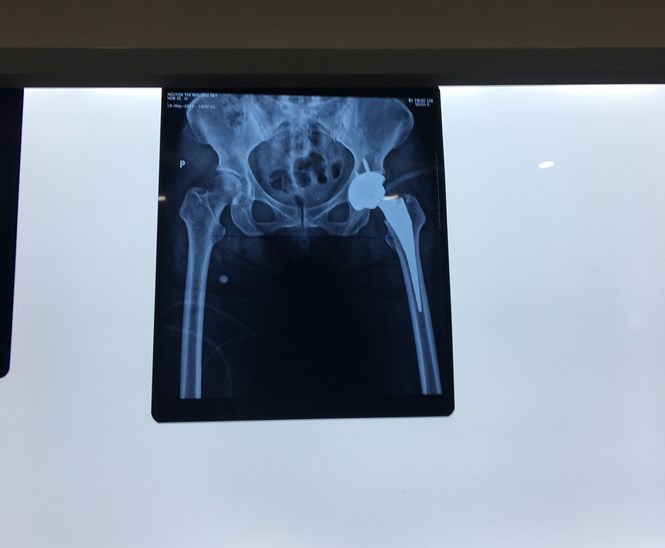

| Hình ảnh chụp X Quang sau khi thay khớp háng |

Kết quả thăm khám cho thấy bệnh nhân bị thoái hóa khớp háng nặng, chân trái bị thoái hóa khớp thấp hơn chân phải 2cm, điều trị bằng thuốc không hiệu quả, nên tư vấn cho bệnh nhân phẫu thuật thay khớp háng toàn phần.